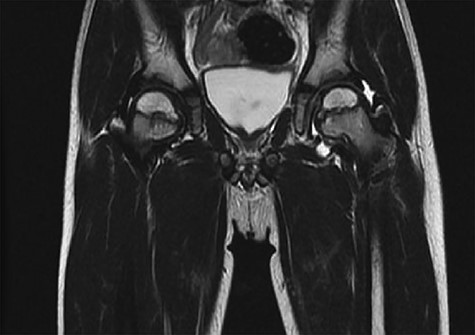

CT hips reported a well-defined lesion seen bilaterally in the neck of femur anterior infero-medial aspect, more prominent on the left side measuring 7 x 3 mm on left side both in coronal (Fig. 3) and axial (Fig. 4) views. On the right side, other lesion measuring 2 x 1 mm (Fig. 5) seen in coronal view. These two lesions are well defined with a sclerotic border with a small cortical defect. The lesion shows fat density. The symmetrical appearance of the lesion combined with the fat density and location suggest the diagnosis of synovial herniation pit. MRI Pelvis revealed minimal left hip joint effusion with loculated fluid seen along the trochanteric bursa with the largest measuring 0.9 x 1.5 cm (Fig. 6, 7).

Showed axial cut of CT hips demonstrating the synovial pit on left and right side.